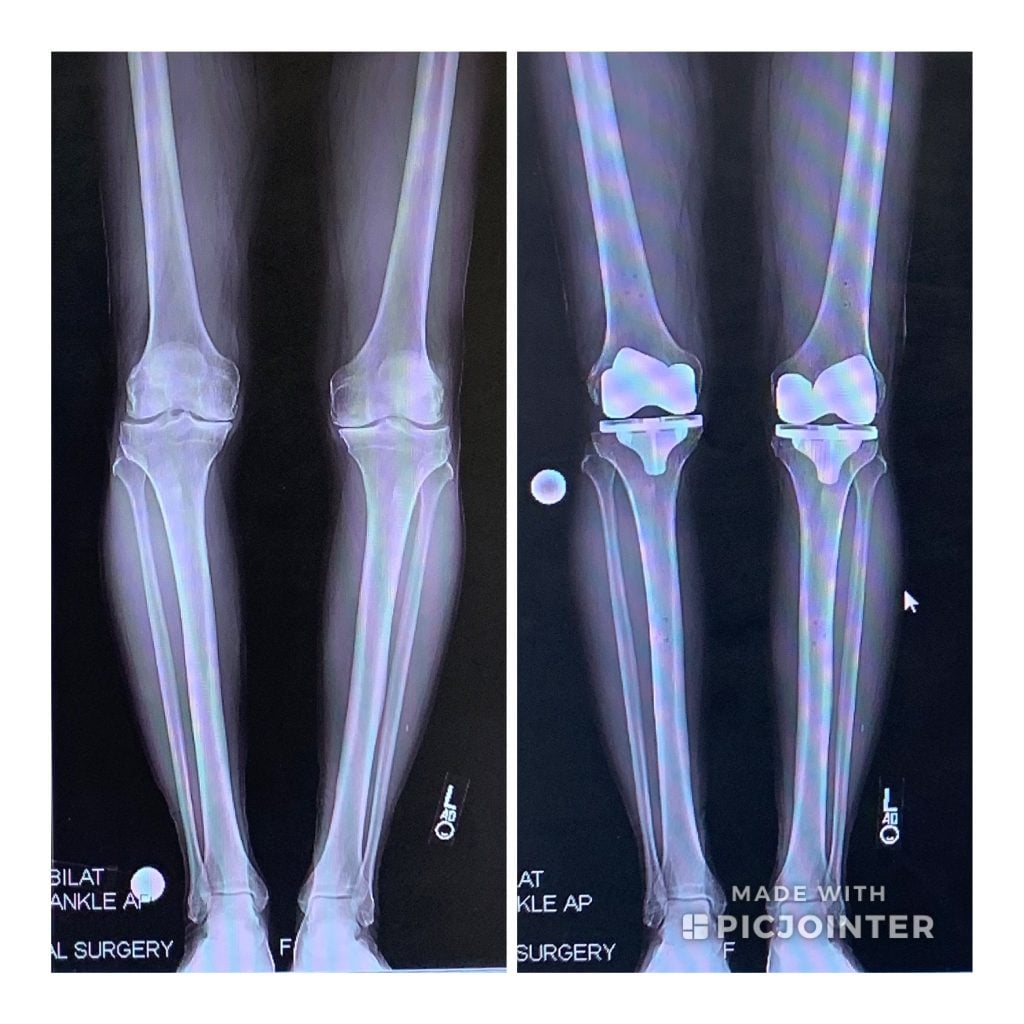

Dr. Caroline Andrew came highly recommended by Dr. Steve Haas, also from HSS. He successfully performed my bilateral knee replacement surgery 20 years earlier. I met with Dr. Andrew in January of 2019. She was attentive. She listened to my long story. She cared. She explained several options. I felt hopeful. She reached out to my team of doctors and discussed the medications I was currently on. She challenged that some medications which promote weight gain could be replaced with more suitable medications which do not. We had a plan. She connected me with Sue Xiao Yu, a nutritionist and together we embarked on a weight loss journey. We met monthly to discuss my progress and to tweak the plan accordingly. By the end of 2019 I lost almost 80 pounds. To date I've lost about 100 pounds and although COVID-19 has affected everyone's lives, I've somehow been able to keep the weight off.